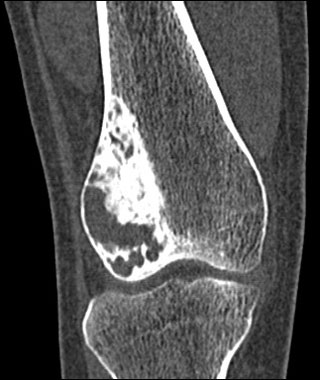

患者,女,32岁,因外伤后右膝疼痛而做ct检查.请大家讨论.有手术病检结果

股骨下端跨越骨骺、干骺端破坏性病变,内上方见多数斑片状钙化,并可见宽窄不一房隔,边缘硬化,无明显膨胀,关节面皮质连续,软组织内无肿块及钙化影。

考虑:软骨粘液样纤维瘤可能性大。

股骨下端跨越骨骺、干骺端破坏性病变,内上方见多数斑片状钙化或骨化,并可见宽窄不一房隔,边缘硬化,无明显膨胀,关节面皮质连续,无骨膜反应,软组织内无肿块及钙化影。

考虑:骨良性肿瘤病变----1成骨细胞瘤。2成软骨细胞瘤。3软骨粘液样纤维瘤。

手术病理结果为“骨良性纤维组织细胞瘤”。

良性纤维组织细胞瘤:又称黄色纤维瘤或纤维黄色瘤。临床症状:主要是疼痛。发病年龄为15~60岁。部位:常在骨干或长骨的关节端,也可在骨盆和肋骨。病程长,可持续数年。

影像学表现:常发生在长骨的两端,均系成年患者。平片和ct为边缘清楚的骨质破坏,可有轻度膨胀,有硬化边缘,病变可呈中心性或偏心性生长,一般无骨膜反应和软组织肿块;mri为等t1、长t2信号。

我们开始也考虑软骨黏液样纤维瘤,该病例确实不典型。特别是肿瘤内侧的多量硬化容易引起误诊。但该病例可能有两点不支持软骨黏液样纤维瘤:(1)年龄偏大,软骨黏液样纤维瘤一般是10~30岁,但无特异性;(2)病变膨胀不明显。水平有限,还请高手指点。